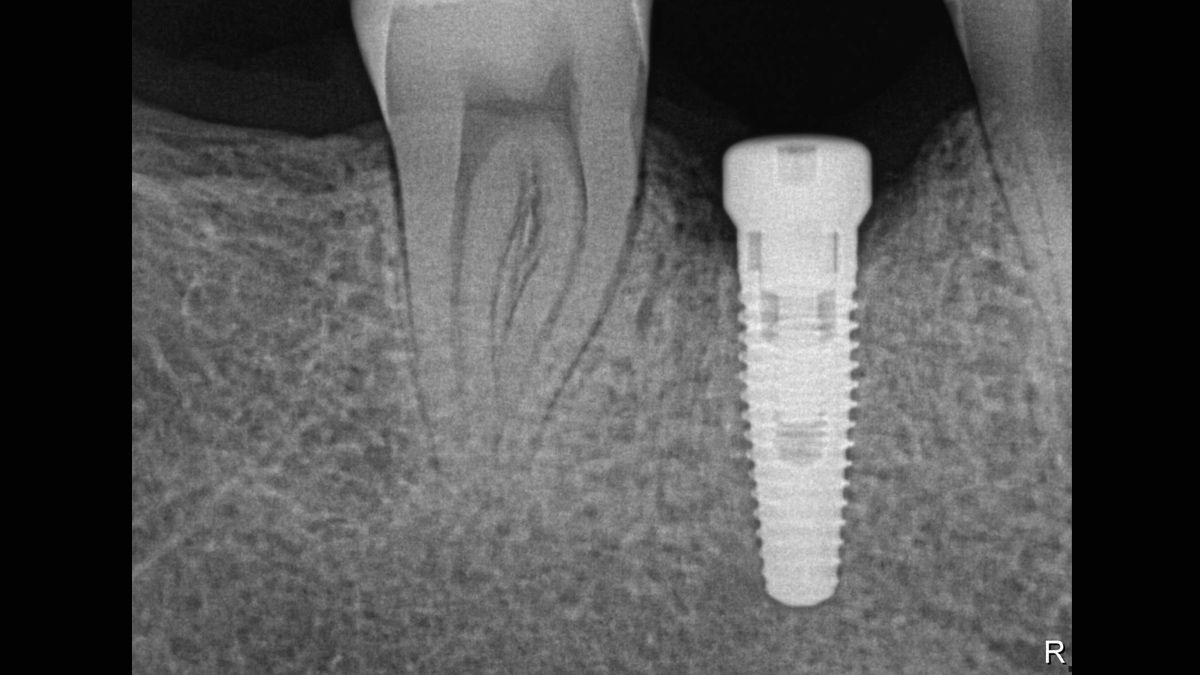

- Doskonała jakość obrazu – teoretyczna rozdzielczość 33 lp/mm (rozmiar piksela 15 μm)

Xios Supreme wyposażony jest w suwak dynamicznego wyostrzania obrazu, co umożliwia dostosowanie ustawień diagnostycznych pod kątem ostrości. Dostępne są również suwaki do modyfikacji jasności oraz kontrastu fotografii. Ustawienia te pozwalają na dostosowanie obrazu odpowiednio do potrzeb prowadzonego leczenia, zwiększając możliwości diagnostyczne oraz usprawniając pracę w gabinecie.

Czujnik posiada funkcję filtrowania z pięcioma dostępnymi opcjami: stomatologia ogólna, endodoncja, periodontologia, odbudowa oraz higiena, które pozwalają na dopasowanie widoku do konkretnej sytuacji klinicznej.

Jest bardziej odporny na zarysowania i zniekształcenia obrazu w porównaniu do elastycznych płytek obrazowych. Umożliwia szybkie przechwytywanie obrazów RTG, charakteryzuje się wyjątkową trwałością.